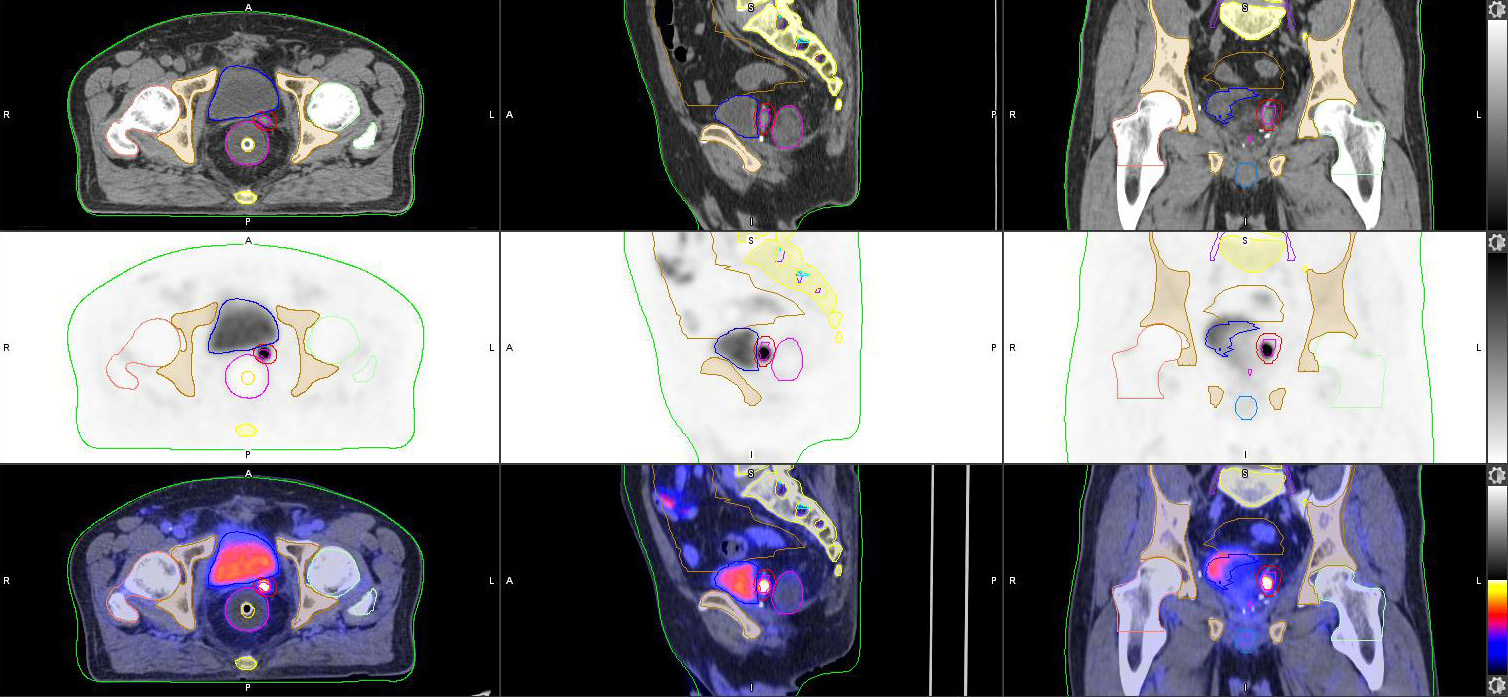

Developed in 2021 PET/CT Simulation is a one-stop imaging facility for both metabolic evaluation and CT simulation in radiotherapy treatment planning. The efficacy of radiotherapy relies on maximizing radiation dose to tumor and preserving normal tissues. With the variety of PET tracers available, PET/CT can delineate the metabolic boundary, quantify aggressiveness and characterize tissue functional status (e.g. cellular differentiation and hypoxia) of targeted tumor.

Our PET/CT scanner with SiPM technology, equipped with an external laser positioning system and a flat indexing pallet, has a precise spatial co-registration and an outstanding image quality. Image data in a single PET/CT scan can streamline the workflow and personalize treatment plan. Biological tumor contours and functional data on PET images can be transferred directly to CT images for dosimetric calculation and dose boosting. It can it be used at pre-treatment stage and within treatment course for interim assessment and adaptive planning.